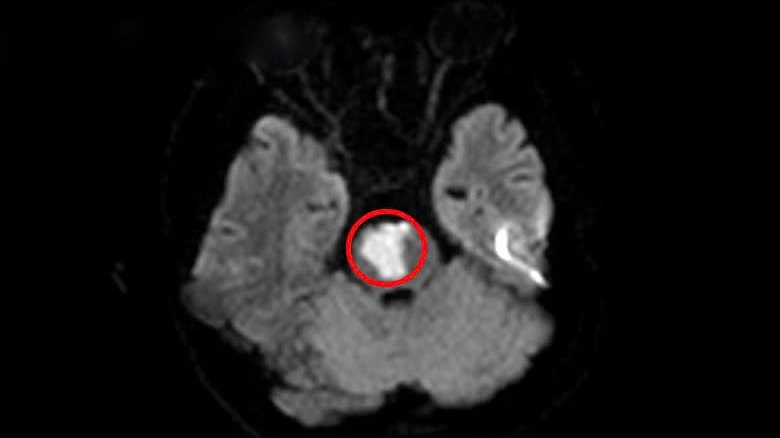

Tại Bệnh viện Đa khoa Xanh Pôn, các bác sĩ phát hiện nam thanh niên bị tổn thương tuỷ sống, yếu tứ chi. Không chỉ vậy, qua chụp cộng hưởng từ, bác sĩ phát hiện bệnh nhân còn bị tổn thương tuỷ ở vùng cổ.

Khí N2O trong bóng cười khi đi vào cơ thể thường gây tổn thương ở vùng tuỷ cổ, dẫn đến tình trạng yếu tứ chi, có thể gây tàn phế đến suốt đời.